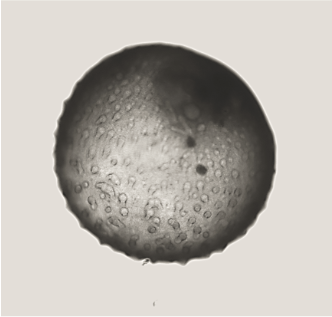

Endometrial organoids for the ReproOrgs project. Credit: Hongorzul Davaapil / Wellcome Sanger Institute.

Hongorzul: We also have a collaboration with Roser Vento-Tormo’s team for two projects. One of the projects is biobanking for endometriosis organoids – called ReproOrgs. Endometriosis is a disease that affects ten percent of women worldwide, but we still have a very poor understanding of how it begins and how to treat it. For this project, we are getting biopsies from a variety of individuals, including those with and without endometriosis, developing organoid models and then banking them at the earliest possible point to hand them over to internal faculty.

In this project, we are also able to isolate, at the same time as organoids, 2D fibroblasts, which are also integral for the biology of the endometrium. So, from one biopsy you end up with two different cell lines. Dr Charlotte Cassie , one of the postdocs in Roser’s group, is very interested in doing a variety of co-culture experiments with organoids and fibroblasts, as well as macrophages and immune cells, which will gradually increase the complexity of the model. Through RNA sequencing, they will hopefully be able to show interesting features about the intricacies of the menstrual cycle and clues as to what might be going wrong in endometriosis.